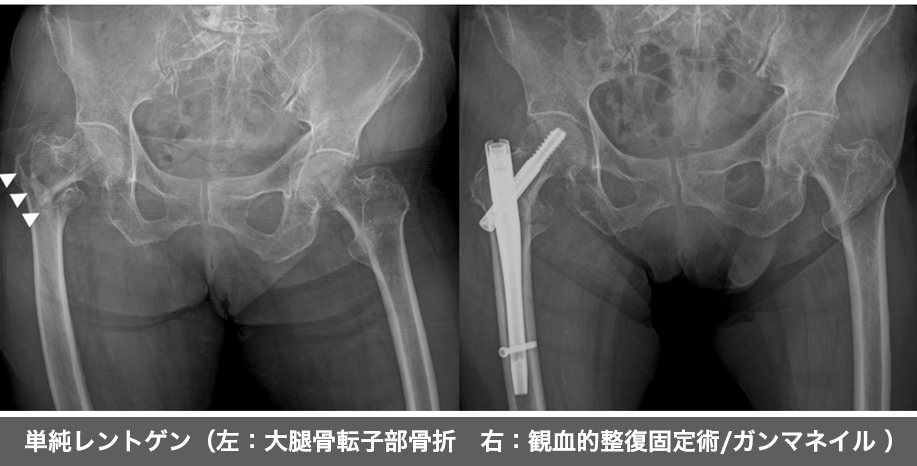

大腿骨には頚部と転子部があり(右図参照)、骨折してしまう場所によって手術方法が変わります。

大腿骨転子部骨折は骨癒合しやすい場所の骨折です。

①観血的整復固定術(ORIF)

骨折した部分を元の形状に整復し、髄内釘などを用いて骨折した部分を安定させる手術です。